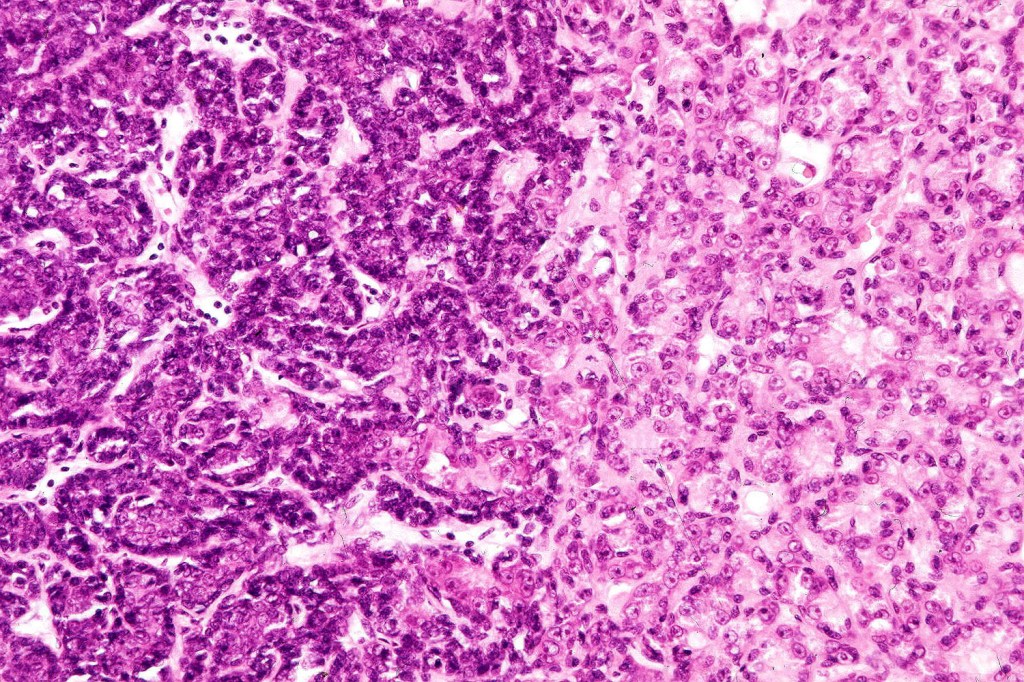

Histological features

•Pre-existent spiradenoma

•Malignant component shows loss of dual cell population, increased mitotic activity, atypical mitoses & necrosis

•Perineural infiltration & LVI may be present

•1. Salivary gland type basal cell adenocarcinoma-like pattern, low grade (BCAC-LG)

•2. Salivary gland type basal cell adenocarcinoma-like pattern, high grade (BCAC-HG)

•3. Invasive adenocarcinoma, not otherwise specified (IAC-NOS)